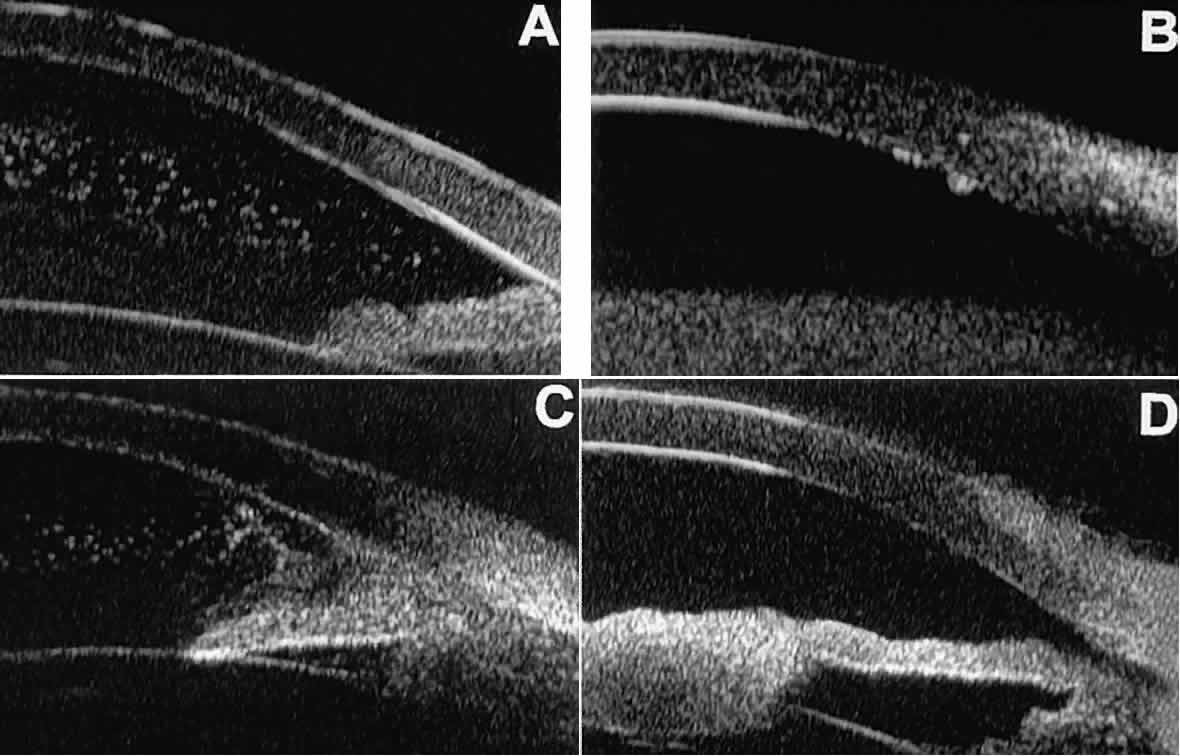

In eyes with a narrow angle, UBM shows the extent of angle closure, reveals the depth of the anterior and posterior chambers, and identifies pathologic processes pushing the lens and iris forward (Fig. 11).2–4,8 UBM has been able to differentiate between primary angle closure (i.e., cases of angle closure without additional pathology responsible for the anterior lens-iris displacement [see Fig. 11A] and secondary angle closure due to processes such as lens swelling and dislocation (see Fig. 11B), massive hemorrhagic retinal detachment pushing the lens and iris anteriorly (see Fig. 11C), and multiple neuroepithelial cysts of the iridociliary sulcus (see Fig. 11D).

Fig. 11. Angle configuration in eyes with angle-closure glaucoma. A. Primary angle-closure glaucoma with anterior displacement of lens and iris. B. Angle closure secondary to swollen, cataractous lens (phakomorphic angle closure). C. Angle closure secondary to massive hemorrhagic retinal detachment; the subretinal blood is evident in the lower right corner of the photograph. D. Angle closure secondary to multiple peripheral iris cysts.